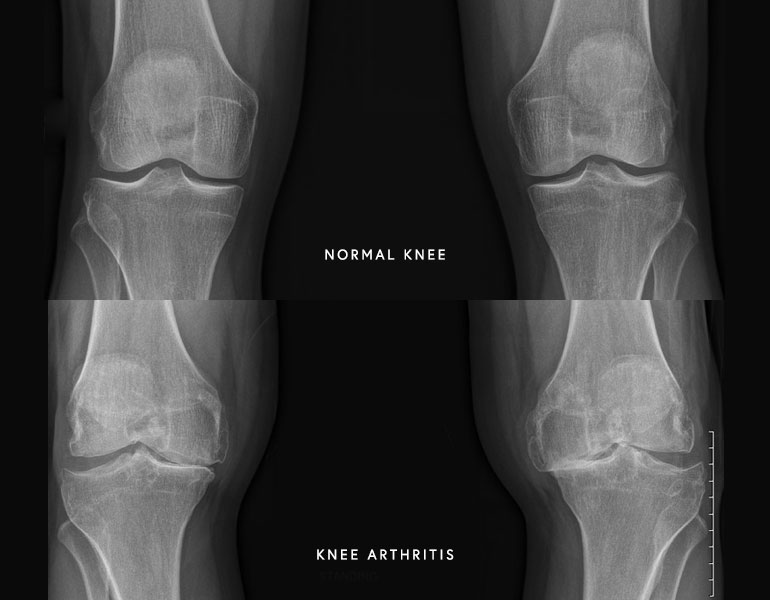

This is wear-and-tear arthritis of the knee that is associated with aging. It is by far the most common type of arthritis. The likelihood of arthritis increases with age, but we can see this in people in their 40’s and 50’s. In this type of arthritis, the cartilage (cushioning at the end of bones) becomes thin and sometimes completely erodes so that the bone surfaces are in contact with each other. This leads to pain and swelling for the patient.

The cartilage surfaces at the end of the femur and tibia wear out, similar to losing tread on a tire. Each of us have nerve endings in the bone so when we lose that cushioning, it can be quite painful.

Dr. Kelly performs a thorough clinical evaluation of each patient that includes three major parts: history, physical examination, and imaging. The history is a focused conversation about duration of symptoms, location of pain, aggravating factors, and previous injuries or surgery to the knee. Next, Dr. Kelly will examine the knee focusing on the overall alignment, range of motion, and any areas of swelling or tenderness. Finally, x-rays of the knee are reviewed which provide additional information about the health of the knee joint. In most circumstances, advanced imaging such as an MRI is not required to make the diagnosis of knee arthritis.